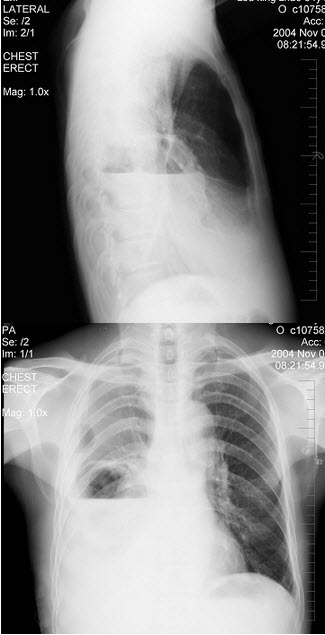

35、单项选择题

男性患者,65岁,因胸痛就诊,胸片检查如图,下列诊断中最明确的是()

A.右肺胸膜肥厚

B.右肺不张

C.右侧胸腔积液

D.右肺炎症

E.右肺肺栓塞